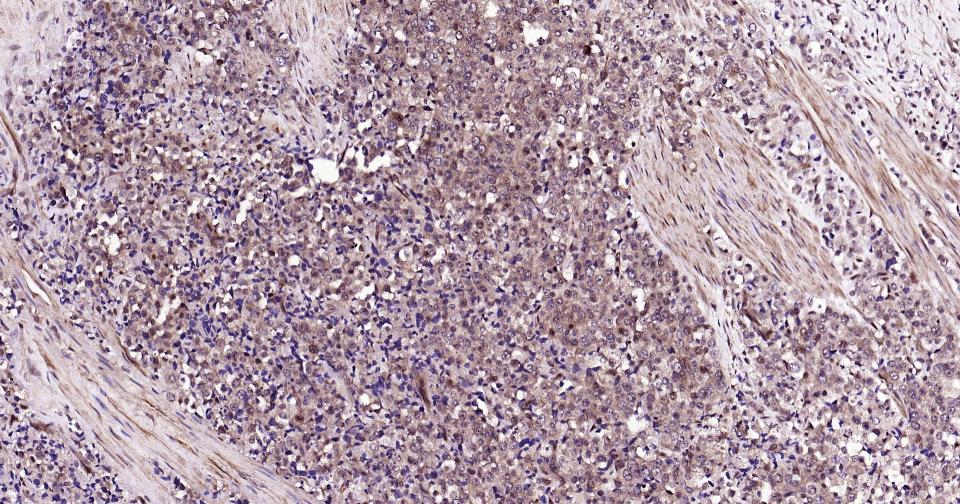

Paraformaldehyde-fixed, paraffin embedded Rat Spleen; Antigen retrieval by boiling in sodium citrate buffer (pH6.0) for 15 min; Antibody incubation with K48-linkage specific ubiquitin? Monoclonal Antibody, Unconjugated(bsm-63005R) at 1:200 overnight at 4°C, followed by conjugation to the bs-0295G-HRP and DAB (C-0010) staining and DAB (C-0010) staining.

Paraformaldehyde-fixed, paraffin embedded Mouse Spleen; Antigen retrieval by boiling in sodium citrate buffer (pH6.0) for 15 min; Antibody incubation with K48-linkage specific ubiquitin? Monoclonal Antibody, Unconjugated(bsm-63005R) at 1:200 overnight at 4°C, followed by conjugation to the bs-0295G-HRP and DAB (C-0010) staining and DAB (C-0010) staining.